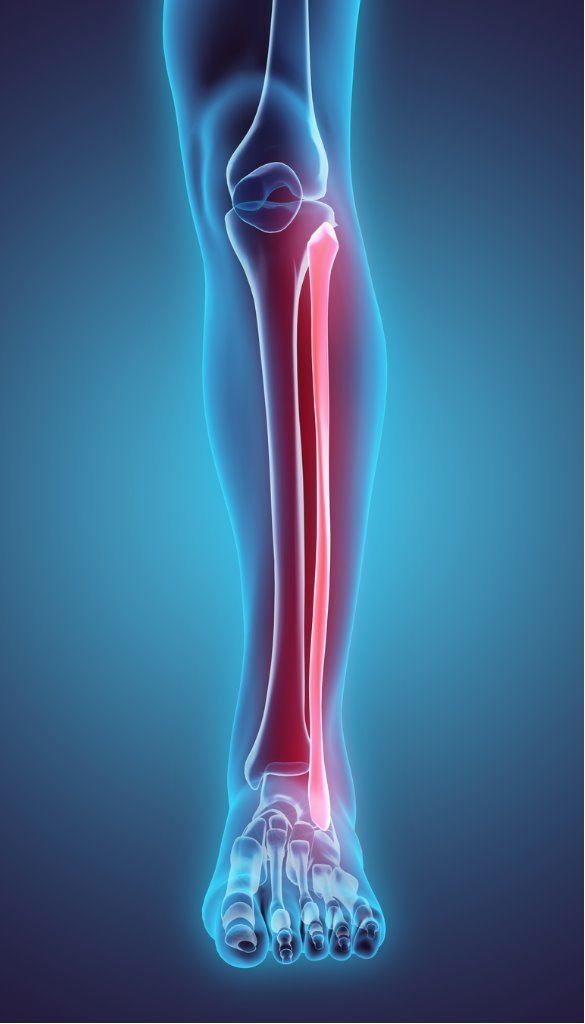

Ankle Injuries with a Fibular Fracture

Ankle injuries can be one of the most difficult injuries to deal with. Since most of our day is spent up and walking around, having an injury to this joint can make many of our simple daily tasks a burden. Ankle injuries are among the most common injuries involving bone and joint. A broken ankle involves fracturing one of the bones that makes up the ankle joint. As clinicians we are often aske by patients, “how to tell if your ankle is broken“. This includes:

- Tibia (the main bone of the lower leg; weight bearing).

- Fibula (the smaller bone on the outside of the lower leg; non-weight bearing).

Fibular Fracture

Fractured Fibula vs Broken Fibula

A broken ankle is considered to be any chip, crack, or break to any of these bones. To learn more about broken ankle symptoms vs an ankle sprain, please go to this Ankle Article. A fractured fibula can be difficult to detect without the use of an X-ray. The Fibula helps in stabilizing and supporting the leg, body, ankle, and leg muscles. Since the Fibula is the outer leg bone and non-weight bearing, many people are still able to walk with this injury. While it will still be difficult moving around, it can be tough to distinguish a fracture from an ankle sprain. Fractures can occur in a variety of ways but typically occur as a result of severe force to the joint, by rolling the ankle on the side, or even extreme flexing or extending of the joint. Fibular fractures can even have many of the same symptoms as a sprained ankle such as: